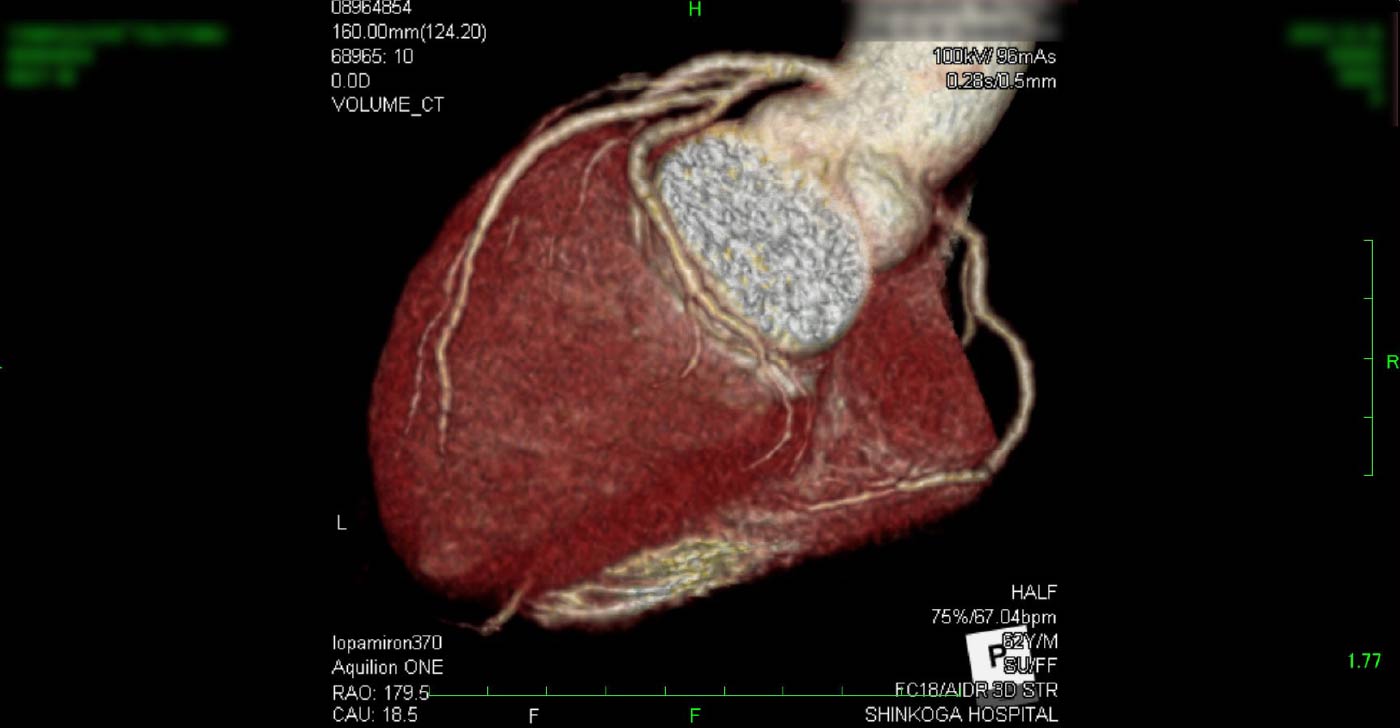

大動脈弁狭窄症

心臓弁膜症の中で、最も重要疾患となる、大動脈弁狭窄症です。意識消失や狭心症のような症状と関連して、突然死に至ることもあります。左室流出路最大血流が、4m/sを超えると、弁置換術の治療選択を考慮しながら管理します。

心エコー3腔像

心エコー5腔像